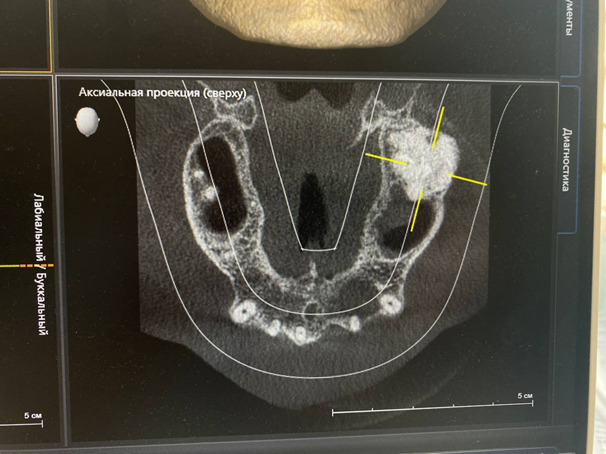

Тут у пациента постоянные клыки и непрорезавшиеся премоляры в верхней челюсти:

А вот ещё более интересный случай. Мы все знаем истории про восьмые зубы, которые уже атавизм. Вот даже пост про них. А тут ещё интереснее:

Справа у пациента есть целый девятый зуб! Это жёлтая стрелка. А синяя стрелка показывает девятый непрорезанный. Девятый зуб поставляется со своим сосудом и нервом. Он имеет все органы и ткани, как у здорового зуба. Он уже с момента образования зачатка соединён с нервной системой, там сосудисто-нервный пучок. Делать с этими зубами пока ничего не надо, надо наблюдать.